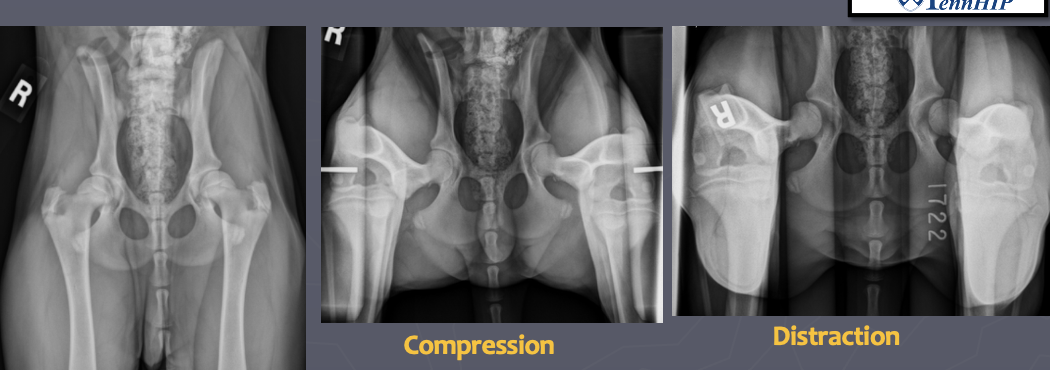

What are the characteristics of PennHIP?

A

-gives a quantitative evaluation of joint laxity

-compares to breed medians

-does not tell you if there is hip dysplasia unless dog has DJD

-examiners must be certified

-requires extended leg VD, compression VD, and distraction VD with distraction apparatus

What is shown in this image?

extended leg VD, compression VD, and distraction VD required for PennHIP evaluation